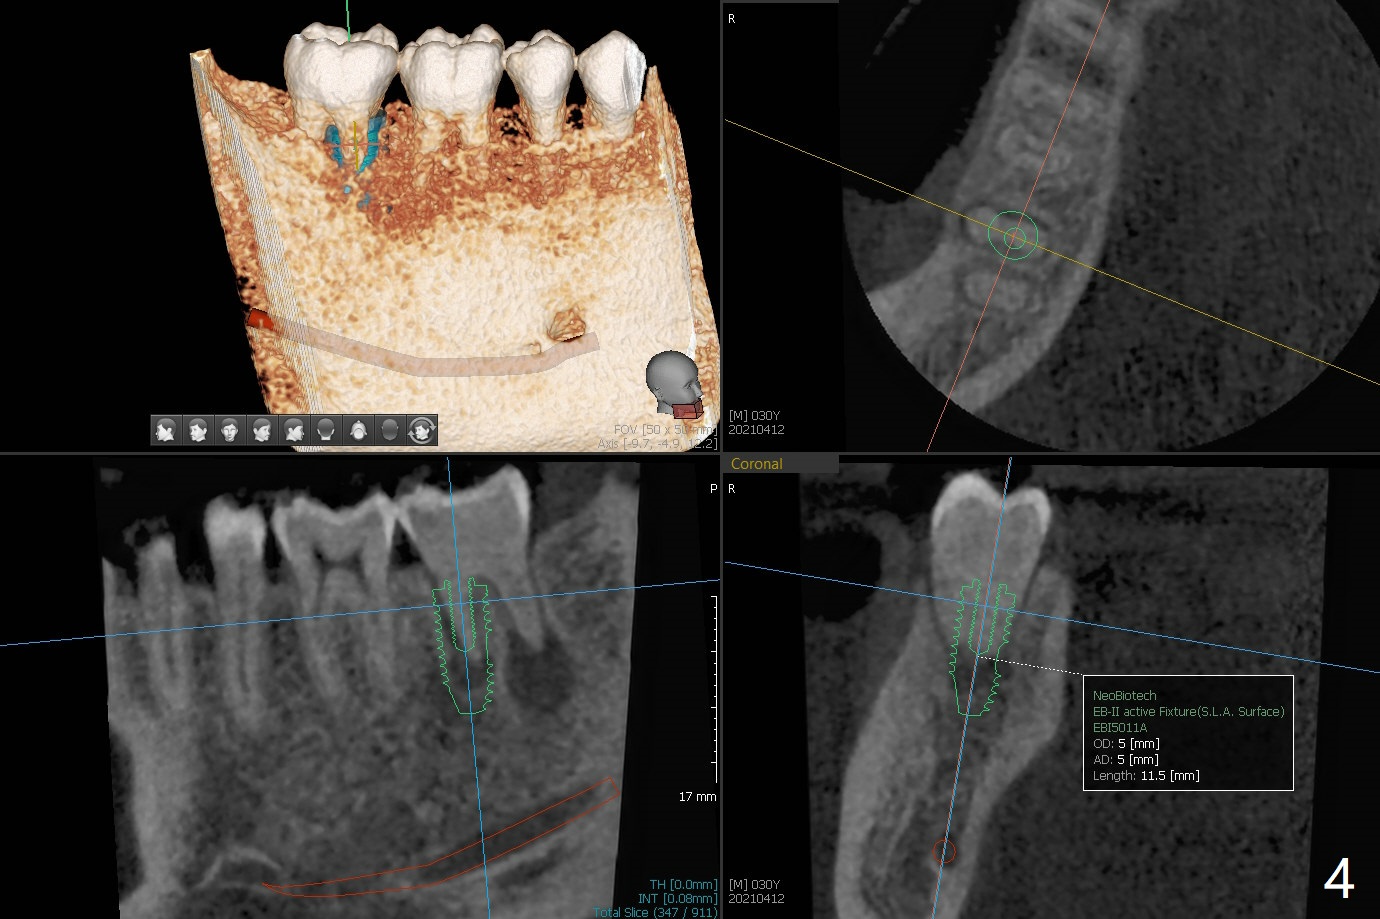

30岁男小的时候双侧下颌第二磨牙埋伏,拔除智齿后,前者经过矫正才萌出。近几年两个第二磨牙都出现疼痛,牙髓病专家认为左侧预后不佳(图一),需要拔除种植(图二)。注意去除根尖肉芽组织。左下7治疗完成后病人要求右下7拔除植牙(图三,四)。